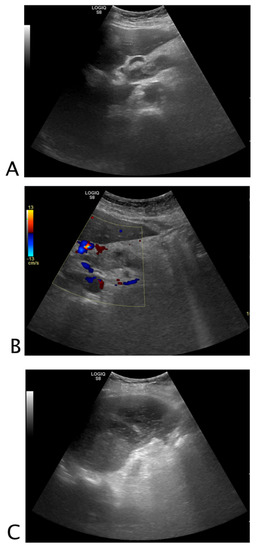

2.2.1. Vessels

2.3.1. Vessels